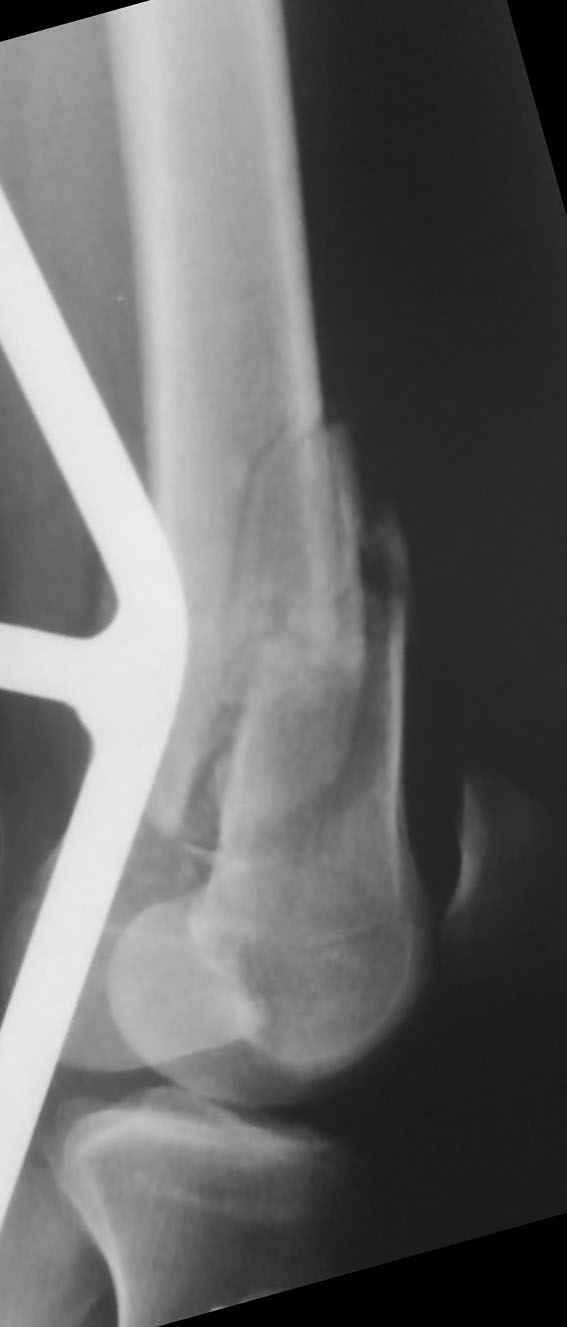

К нам поступил пациент 25 лет с закрытыми переломами обех бедренных

костей, прошел месяц после травмы. Слева-внутрисуставной перелом,

поэтому  выбор здесь очевиден, открытая репозиция, стабильная

фиксация, скорее всего LCP DF, а справа - мнения учёных, как

говорится, разошлись. Лично я, как лечащий врач, за закрытый

интрамедуллярный остеосинтез DFN. Со мной согласна половина

коллектива, другая - за интрамедуллярный остеосинтез (DFN,UFN) но с

открытой реопозицией, поскольку при закрытой методике все осколки

останутся где-то сбоку, получится дефект и вдруг не срастется!